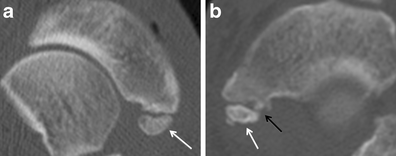

Degeneration at a synchondrosis. a Long-axis axial CT image shows an apparently normal type II accessory navicular (arrow) with a preserved synchondrosis with the navicular tubercle. b In comparison, this long-axis axial CT image of a different foot depicts increased sclerosis and fragmentation of a type II accessory navicular (white arrow) and fragmentation of the navicular tubercle at the synchondrosis (black arrow) consistent with degenerative change

Degeneration at a synchondrosis. a Long-axis axial CT image shows increased sclerosis (black arrow) and subchondral cyst formation in an os trigonum. b Sagittal CT image reveals subchondral cyst formation in the talus (black arrow) and os trigonum (white arrow) across the synchondrosis, due to degenerative change